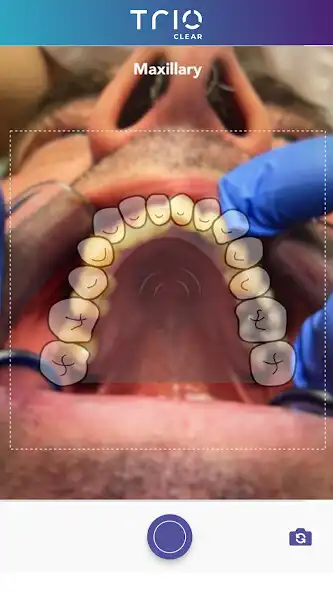

- Capture and save required photos on the App for case submissions later on the TrioClearTM Doctor Submission Portal.

- View all the patient profiles, photo records and treatment status.

- Keep track of treatment progress with photos and aligner wear time stats submitted by patients at different stages if necessary.